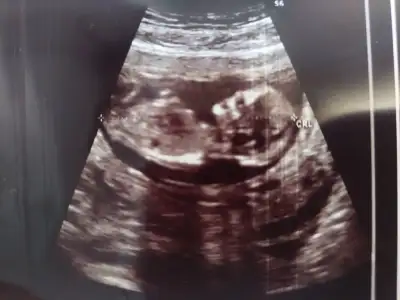

Evet canım cinsiyet öğrenme olasılığın yüksekKızlar Nasılsıniz benim yarın ikili test ve doktor kontrolum var en son mart sonu gitmiştim 1 ay olacak yarın 12 artı 2 ama ultrasonda 3 4 gün önde gidiyordu bakalım inşallah sağlıkla güzel haberler alırız kontrole giden test yaptiran veya cinsiyet öğrenen var mi

Canım ben 11+5te gitmiştim gelişim 6 gün önde çıktı 12+4tü. Cinsiyet için de yüzde 70 kız dedi. Sonra 14.haftamda devlet doktoruna gittim biraz ısrar ettim söylesin diye. Erkek bence bu dedi neyse 16da netleşir dedi. Yani 12de söyleyebilir ama çok da kesin konuşmaz muhtemelen. Sonra değişebilir benimki gibiKızlar Nasılsıniz benim yarın ikili test ve doktor kontrolum var en son mart sonu gitmiştim 1 ay olacak yarın 12 artı 2 ama ultrasonda 3 4 gün önde gidiyordu bakalım inşallah sağlıkla güzel haberler alırız kontrole giden test yaptiran veya cinsiyet öğrenen var mi

Kesin erkek mi yani canımCanım ben 11+5te gitmiştim gelişim 6 gün önde çıktı 12+4tü. Cinsiyet için de yüzde 70 kız dedi. Sonra 14.haftamda devlet doktoruna gittim biraz ısrar ettim söylesin diye. Erkek bence bu dedi neyse 16da netleşir dedi. Yani 12de söyleyebilir ama çok da kesin konuşmaz muhtemelen. Sonra değişebilir benimki gibi![]()

Doktora başta cinsiyeti ne diye sordum. Bu haftalar daha erken yanılmalar çok oluyor dedi. Ben de ısrar ettim bi baksanız dedim bi öncekinde kıza benziyor demişti doktor dedim. O da öyle olunca hadi bakıyım bi moduna girdi baktı böyle bacak arasına doğru. Ama ben çok göremedim ekstra bi ekran yoktu çünkü. Sonra da "erkek. Benim tahminim o yönde bi sonrakine netleşir" dedi. Ama bence net gördü de işte. Şimdi baştan netleşmez falan dediği için, bir de diğer doktor kız dediğinden sorumluluk almamak için. Tahmin dedi yani. Ama suratından net bir erkek çıktı başta. Sonra dedi tahmin ama 16dan Sonra net oluyor falan dedi. 14te erkekler kendini net belli ediyor ama ben o yüzden erkek olduğunu düşünüyorum. Kendi doktoruma da 16+2de randevum var. Yani 2 hafta sonra. Bakalım kız derse şok olurum yani erkek gibi görüyorum artıkKesin erkek mi yani canım